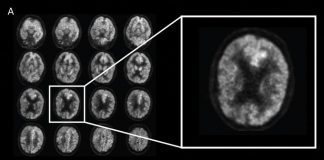

“코로나 후유증 세로토닌 고갈과 관련 있다”

신종 코로나바이러스 감염증 후유증 '롱 코로나'(Long COVID)가 세로토닌..